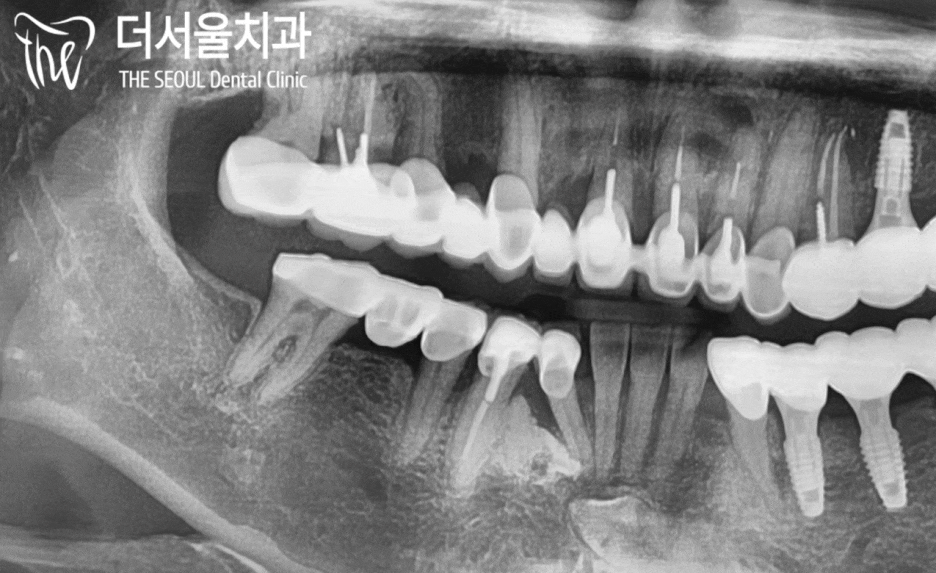

구강 내를 살펴보면 오래된 브릿지가

어금니 부근으로 자리를 잡고 있었는데요.

정밀검사를 하기 전에도 알 수 있었습니다.

바로 ‘이차우식’이 생겨 통증이 생겼다는걸요..

파노라마로 좀 더 자세히 살펴볼까요?

주변 치조골이 다른 곳에 비해

약간씩 오목하게 들어가 있는 것을 확인할 수 있죠.

염증이 진행되어 잇몸, 그리고 잇몸뼈까지

악화시킨 것으로 판단이 됩니다.